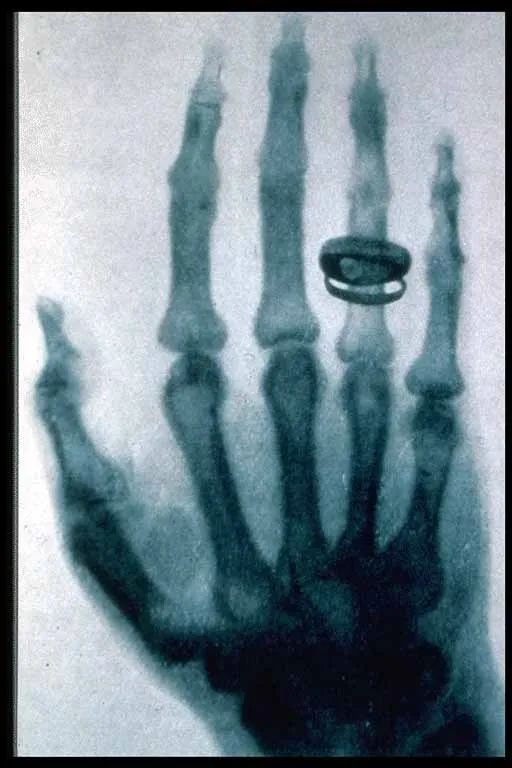

这张照片想必大家不会陌生,是人类历史上的第一张X光片,但你知道它是怎么来的吗?今天,小编就来讲讲这张X光片背后的故事。

伦琴的工作环境十分简陋,一个不大的实验室,窗下是张大桌子,左边是个木架子放着日常用品,前面是个火炉,右边放着高压放电仪器。1895年冬的一天,伦琴把实验室的门关的紧紧的,一个人在那里进行阴极射线的研究。实验时他发现了一种新的射线,这种射线可以穿透书本、玻璃、木头、硬橡胶、衣服和人体的血肉等轻物质,但金属和人的骨骼等重物质则会挡住这种射线。他如痴如醉地投入试验,一连数日没有回家。当他的夫人生气地到实验室找他时,伦琴什么也没说,而是把他夫人的手放到包着黑纸的底片上,然后将阴极射线管通上电,用新射线照了一下。底片冲出来后,伦琴夫人惊叹不已,问:“这个圆环是什么?”“是我们的结婚戒指!”伦琴用代表未知的X命名了这种新射线,由此,X射线登上了历史的舞台。